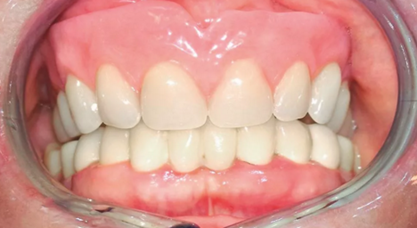

在對(duì)義齒的位置進(jìn)行最終調(diào)整后,制作覆蓋義齒(圖11)。試戴覆蓋義齒,達(dá)到咬合平面,臨時(shí)決定暫時(shí)僅安裝4個(gè)Preci附件中的2個(gè),以便于患者更容易適應(yīng)義齒。3周后將所有覆蓋義齒中的配件安裝完畢。

(圖11)